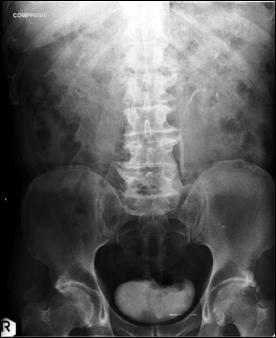

Diagnosticul diferential cu tumori vezicale secundare

a). Adenocarcinomul de colon sigmoid ce invadeaza vezica urinara

a. b.

Adenocarcinom de colon sigmoid

b). Neoplasm de col uterin, invaziv in vezica urinara

a) Tumora de col uterin, invaziva in vezica urinara - pacienta s-a prezentat in anurie; b) Tumora de col uterin, operata (histerectomie totala + iradiere), recidivata, invadand vezica urinara si rectul - pacienta s-a prezentat cu hematurie

c). Neoplasm de prostata care sangereaza

Figura 66. Pacient cu neoplasm de prostata, anurie si hematurie.